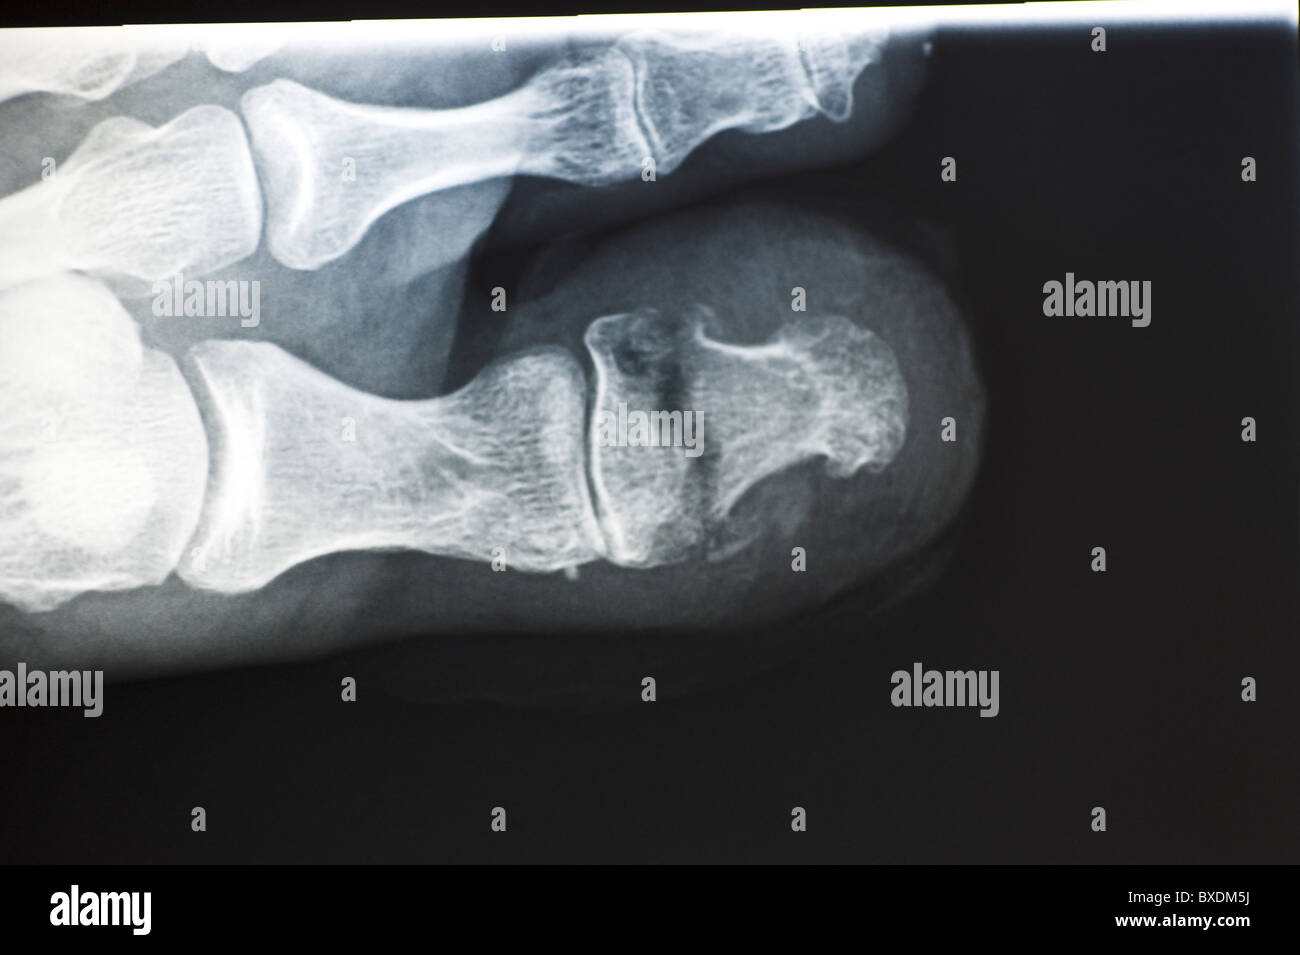

RMBR4J1F–Fuß Röntgen einer 53 Jahre alten Frau, die ihren Fuß schlug und der proximale Phalanx von ihrem kleinen Zeh gebrochen